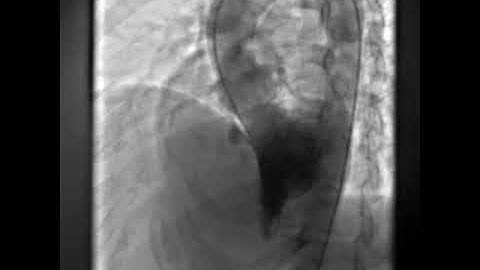

1 Perimembranous VSD Device Closure LV Angiogram